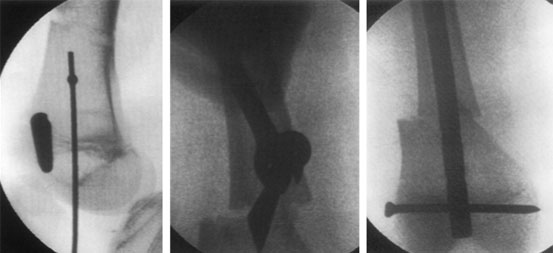

| Percutaneous osteotomy is performed using minimally invasive technique through a small incision, just enough to permit the osteotome with minimal soft tissue stripping. The pictures here show the xrays done during surgery. Drill holes are made using the jig. The entry path for the nail in the distal part of the bone is marked using k-wire and cannulated drill bit. Another instrument like osteotome is used to mark the correct angle. The holes are then connected and osteotomy is completed using the osteotome. |

| These are x-ray pictures taken during surgery. The left one shows the path of entry of the guide wire as seen from the side. The picture in the center shows how the bone is translated(shifted on the long axis) at the osteotomy site. This is done in accordance with osteotomy rule 2(i.e when the osteotomy is away from the CORA-center of rotation axis.) The picture on the right shows the final picture after the insertion of the intra-medullary nail in the corrected position with locking bolt holding the nail to the bone. |